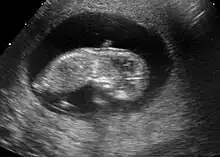

Embryon à 8 semaines

L'embryon mesure entre 15 et 22 mm. La vésicule vitelline qui le nourrit est juste à côté. À la fin de cette semaine, les coudes deviennent visibles